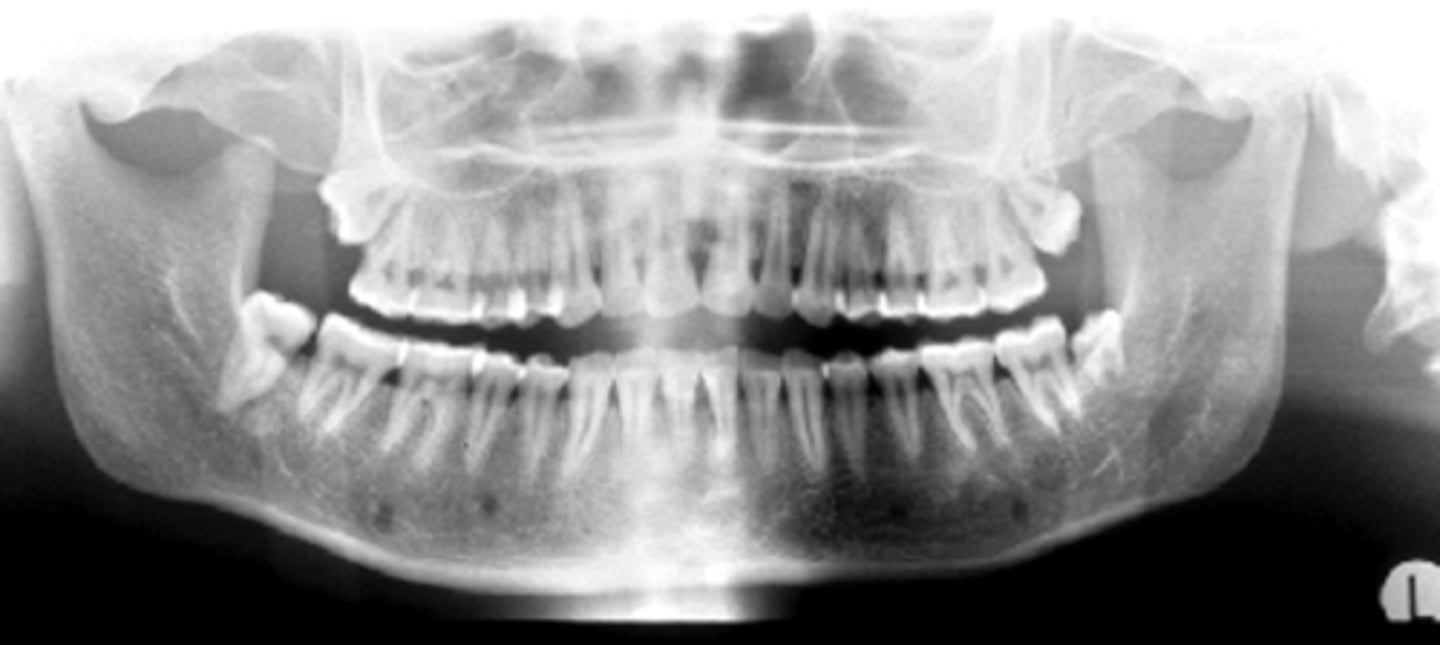

ID the positional error from the radiograph:

right rotation (pts right side is larger)

(And too far back)